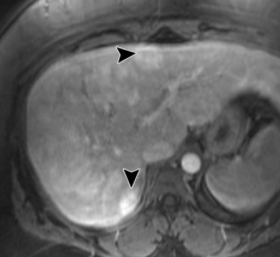

Sous-type HFN1a-muté

- Beaucoup de graisse intracellulaire

- HyperT2 intermédiaire

- Wash-In très moderé, s’homogénise en veineux

- Perte de signal en In/Op

- rehaussemnt artériel moderé, pas veineux

- Saigne peu et se transforme peu (découverte fortuite++)